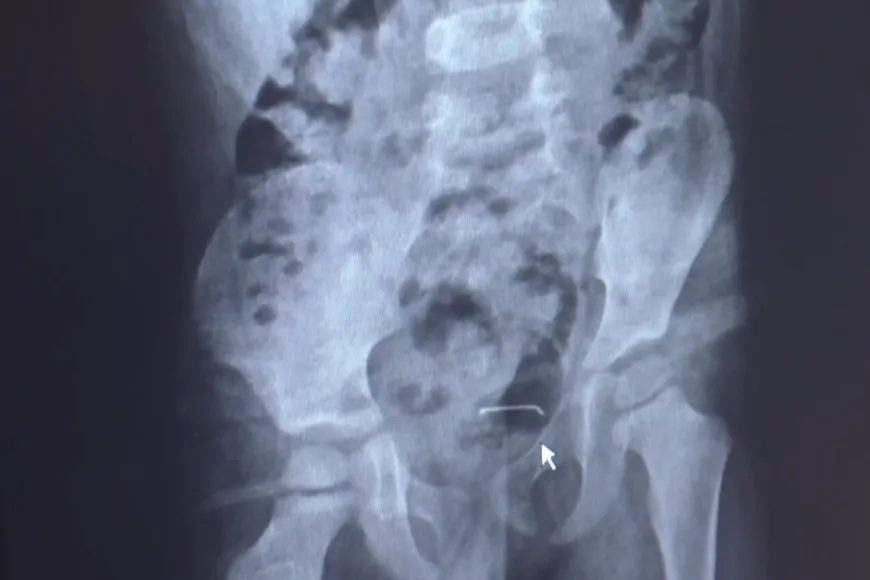

Bitlis’in Güroymak ilçesinde karın ağrısı şikayetiyle hastaneye götürülen 5 yaşındaki çocuğun mesane duvarında metal bir cisim tespit edildi. Yapılan ameliyatla, çocuğun 9 ay önce yanlışlıkla yuttuğu toplu iğne çıkarıldı.

Ailesi tarafından daha önce birçok sağlık kuruluşuna götürülen ancak teşhis konulamayan çocuk, son olarak 4 gün önce Tatvan Devlet Hastanesi’ne başvurdu. Burada yapılan tetkiklerde, mesane duvarında 3 santimetre büyüklüğünde bir toplu iğne olduğu belirlendi. Çocuk Cerrahi Uzmanı Op. Dr. Tahsin Onat Kamçı tarafından ameliyata alınan çocuğun mesanesindeki iğne başarılı bir operasyonla çıkarıldı.

Op. Dr. Kamçı, hastanın 9 ay önce bir cisim yuttuğunu ancak ailesinin bunun toplu iğne veya çivi olup olmadığını ayırt edemediğini söyledi. Yapılan muayenelerde cismin vücuttan doğal yollarla atılmadığını fark ettiklerini belirten Kamçı, şu ifadeleri kullandı:

“Bunun üzerine ameliyat kararı aldık. Operasyonda cismin mesane duvarına yapıştığını gördük. Cerrahi müdahaleyle 3 santimetrelik toplu iğneyi çıkardık. Hastamızı birkaç gün takip ettikten sonra sağlık durumu iyi olduğu için taburcu ettik.”